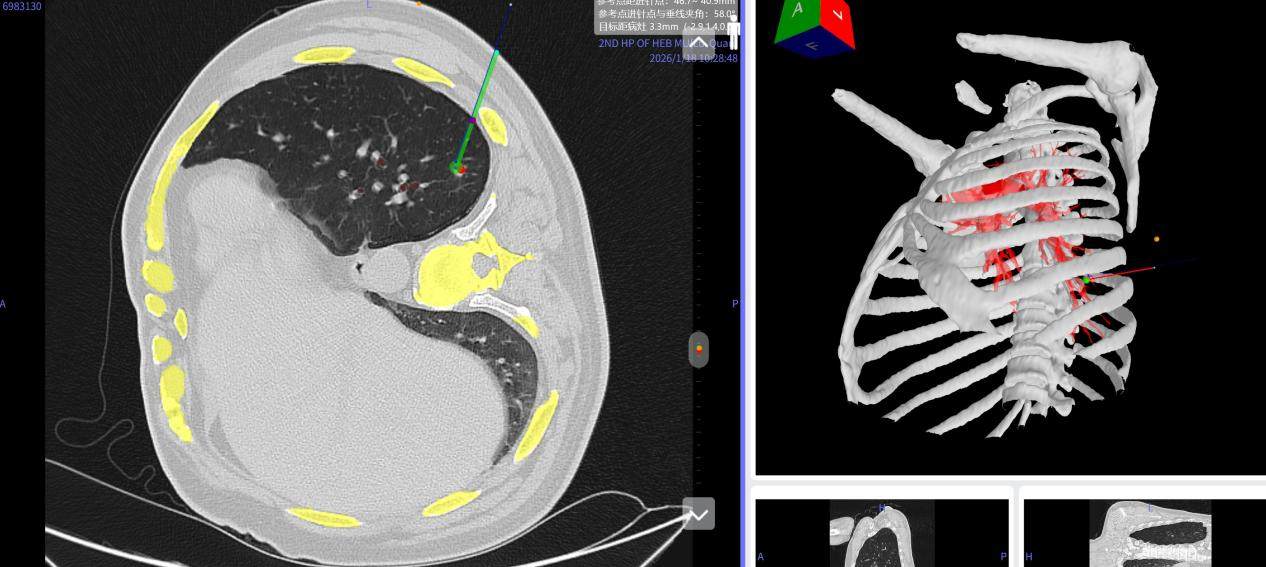

患者56岁,CT检查发现左肺下叶存在肺小结节。治疗通常需在CT引导下进行肺结节定位,但在实际操作中面临挑战:胸部肋骨、肩胛骨的遮挡,肺内丰富的血管及支气管分布,呼吸运动导致的结节位置变化等,均增加了定位难度。此外,操作过程中常需多次CT扫描以调整定位针位置,并在患者清醒状态下进行,会伴有一定疼痛与焦虑,也存在空气栓塞、气胸等潜在风险。综合考虑上述因素,李书军团队最终选择采用AI-AR导航设备,为患者实施左侧卧位导航下术中定位术。

手术当日,患者接受全身麻醉后取侧卧位。李书军教授佩戴VR眼镜开始实施定位。在人工智能技术的驱动下,患者的肋骨、支气管、肺组织及血管等胸部结构,连同其呼吸动态,均以三维立体的形式实时呈现在视野中。

借助虚拟与现实融合的手术场景,医生将视线聚焦于患者病灶区域,通过调整视角精准锁定结节位置。随后手持一枚“伞形”三维标识定位穿刺标记物,依照系统导航提示,沿术前规划好的穿刺路径,精准避开肋骨与血管,将标记物顺利送达目标位置并释放。该“伞形”标记物采用自膨自锁的钝形设计,释放时可瞬时轻柔地推开周围组织与血管,不仅降低了出血风险,也实现了更稳固的锚定。整个定位过程仅用时不到5分钟。